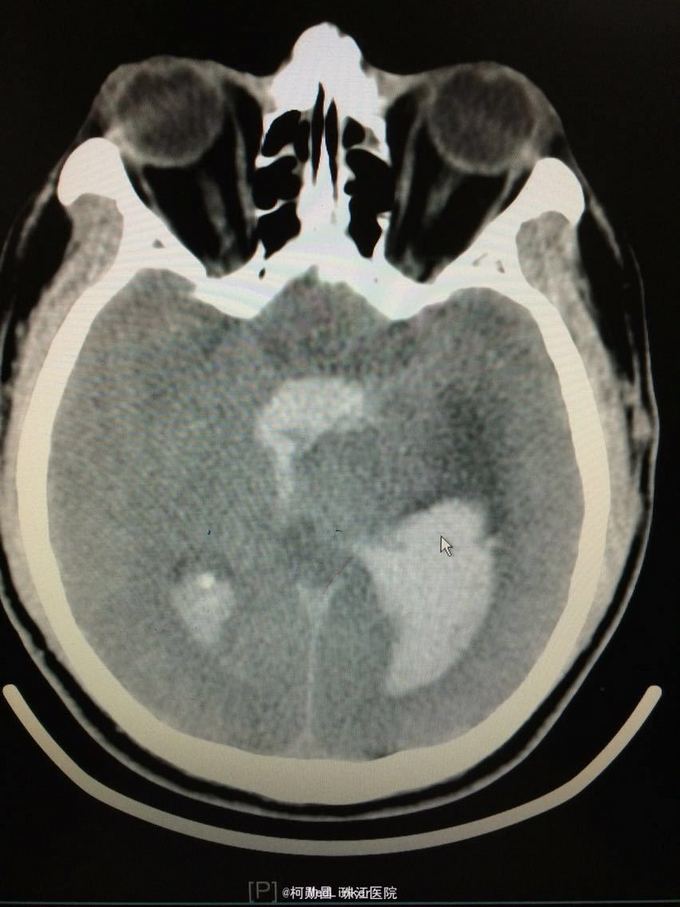

主诉:突发意识障碍4小时 病史:患者57岁男性,入院前一天晚上突发意识不清,伴呕吐胃内容物多次,无肢体抽搐等,随即由家人呼叫120送至我院,急诊行头颅CT提示左侧基底节区出血破入脑室。既往高血压病史10多年

查体:神志不清,双侧瞳孔散大,对光反射消失,四肢肌张力正常,肌力无法检查 辅助检查:头颅CT提示左侧基底节区出血破入脑室

诊断:左侧基底节区出血并破入脑室 处理:急诊行侧脑室钻孔外引流术,术后并予积极抢救,最终抢救无效死亡